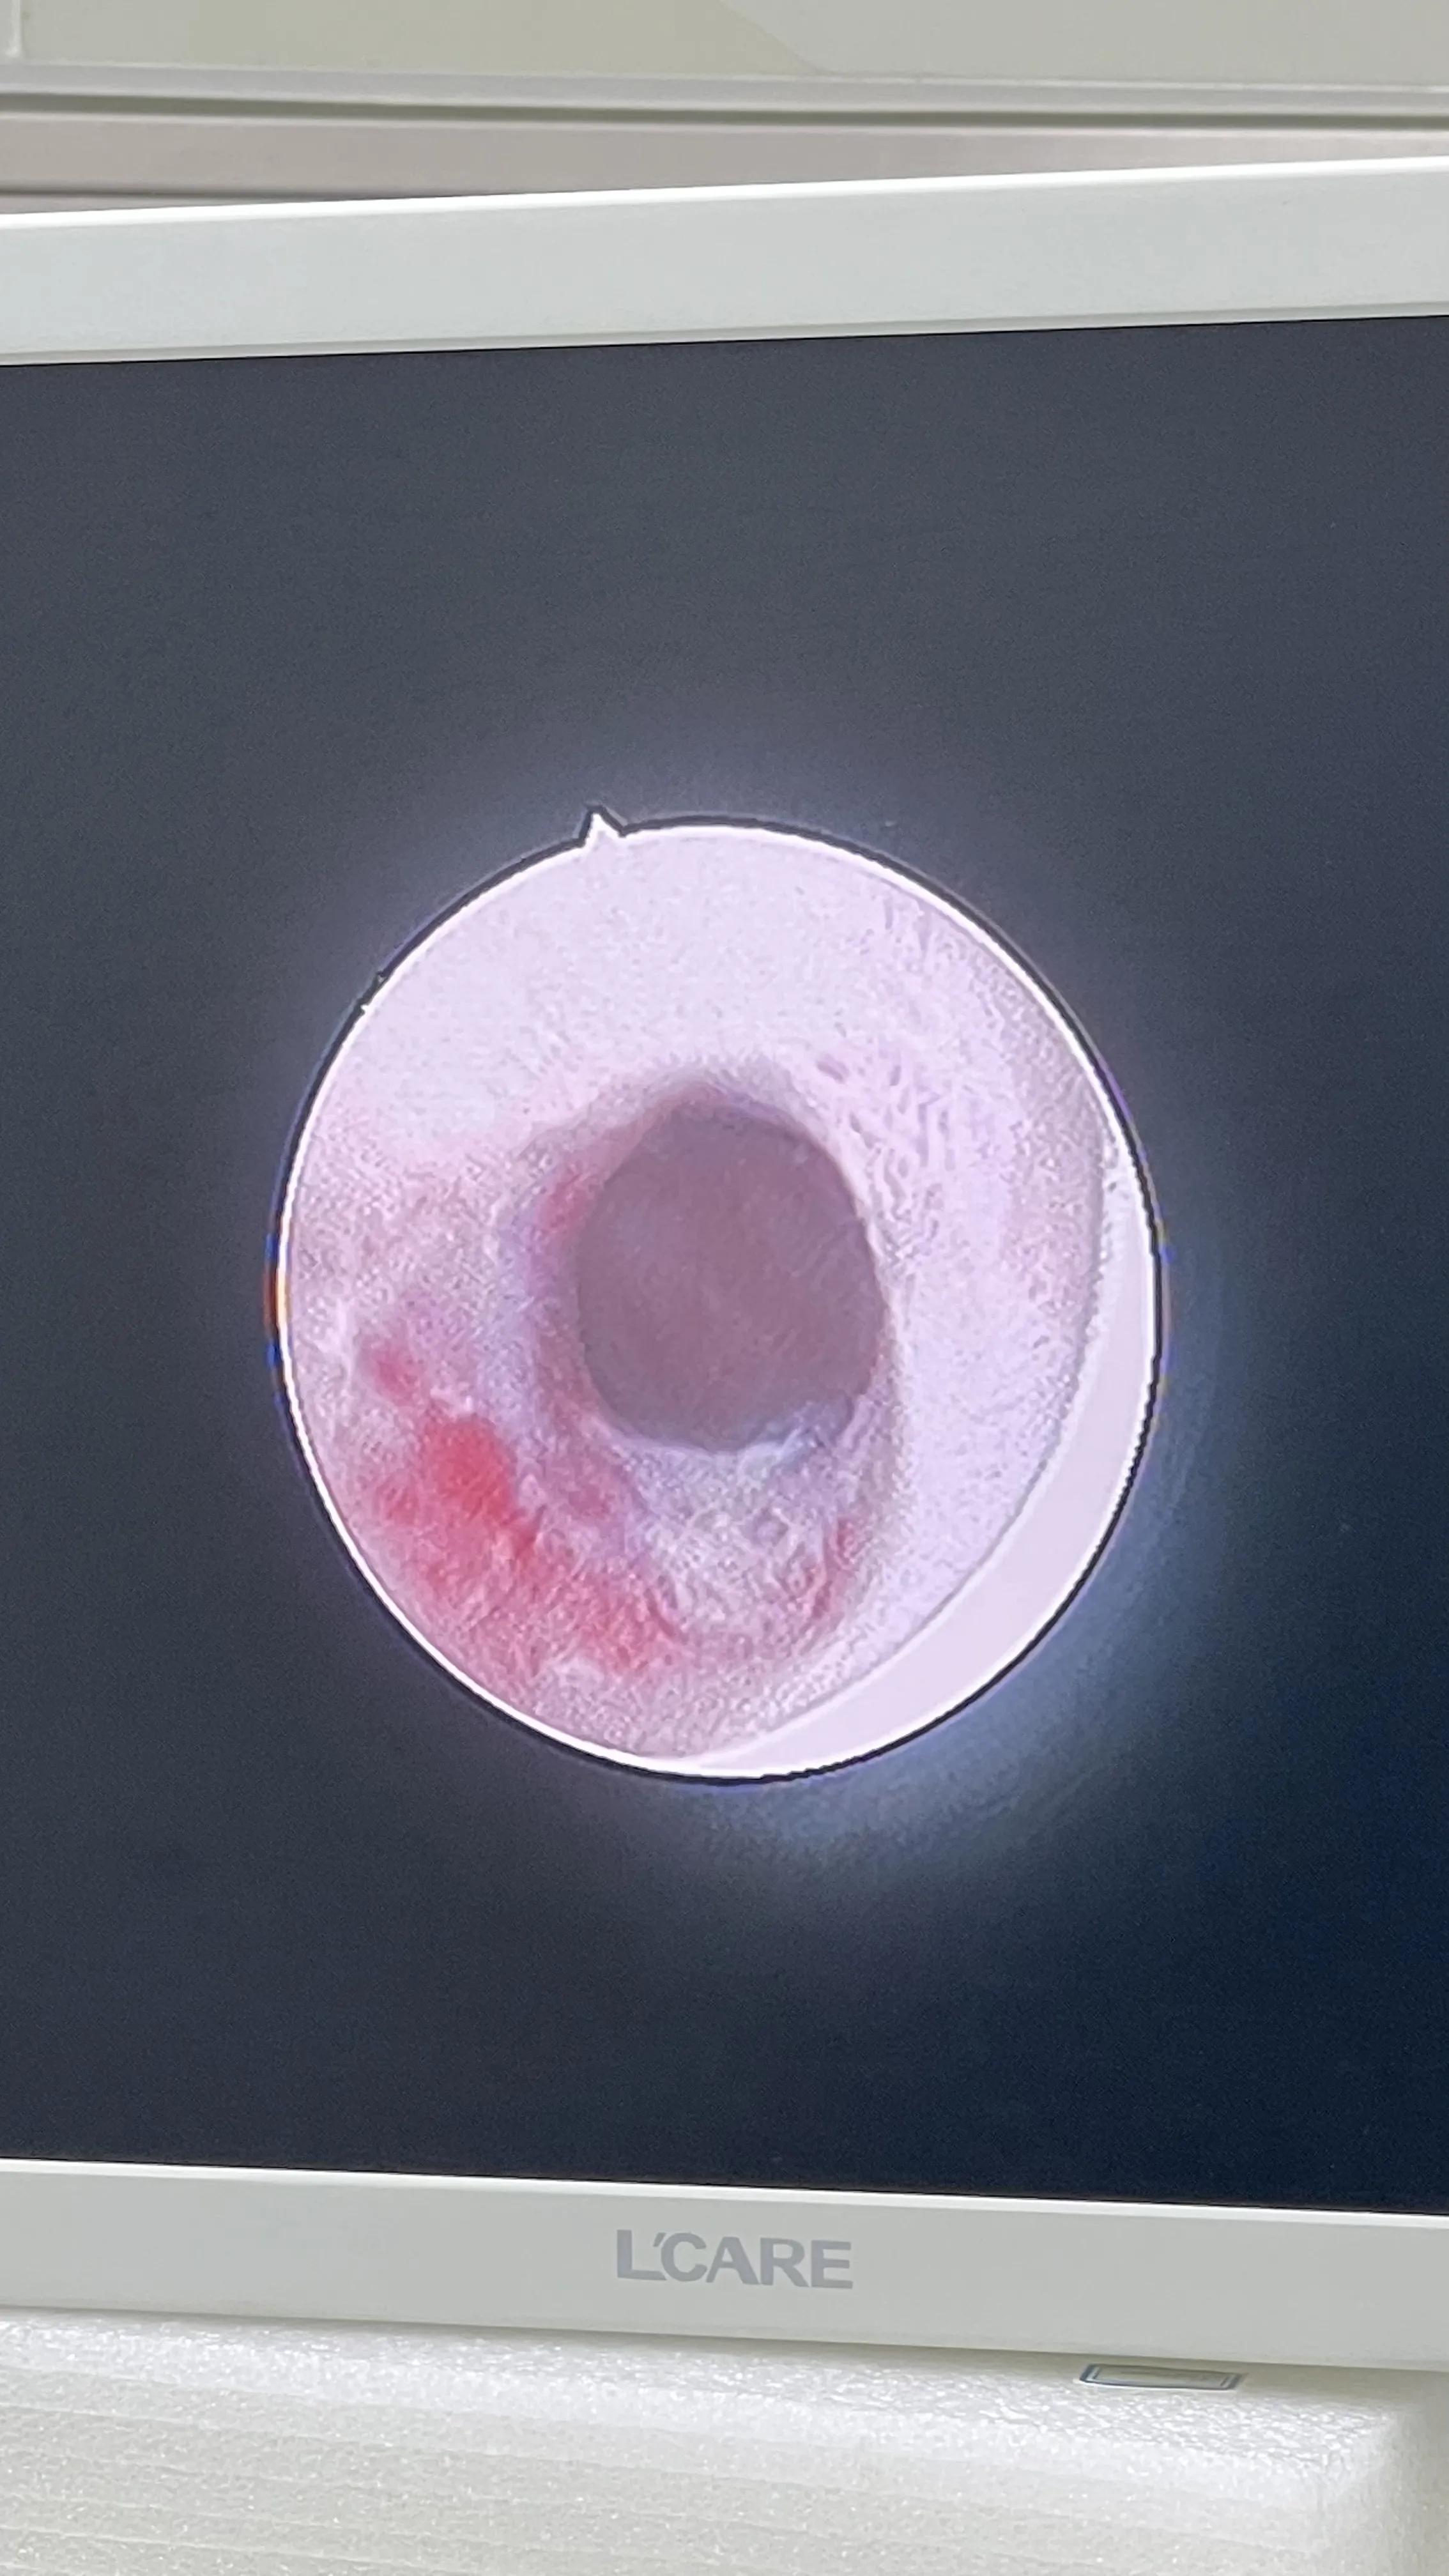

由于患者膀胱造瘘1年零8个月,膀胱造瘘管拔除后,膀胱造瘘口没有完全愈合,今天开放手术切除膀胱腹壁瘘。麻醉后顺便复查尿道镜检查,尿道通畅,F20中号尿道镜顺利通过(图四、图五)。

图四 患者治愈,复查尿道镜,膜部尿道通畅

图五 患者治愈,复查尿道镜,精阜清晰